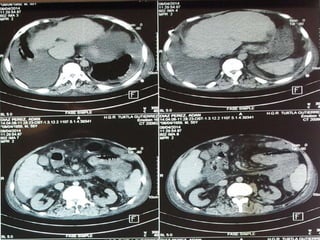

Diagnósticos